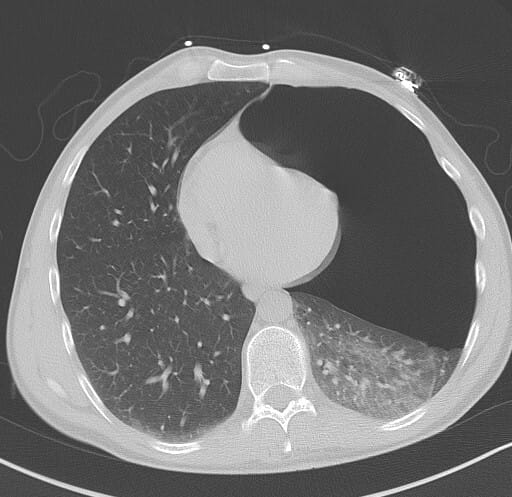

CT에선 이렇게 보입니다.